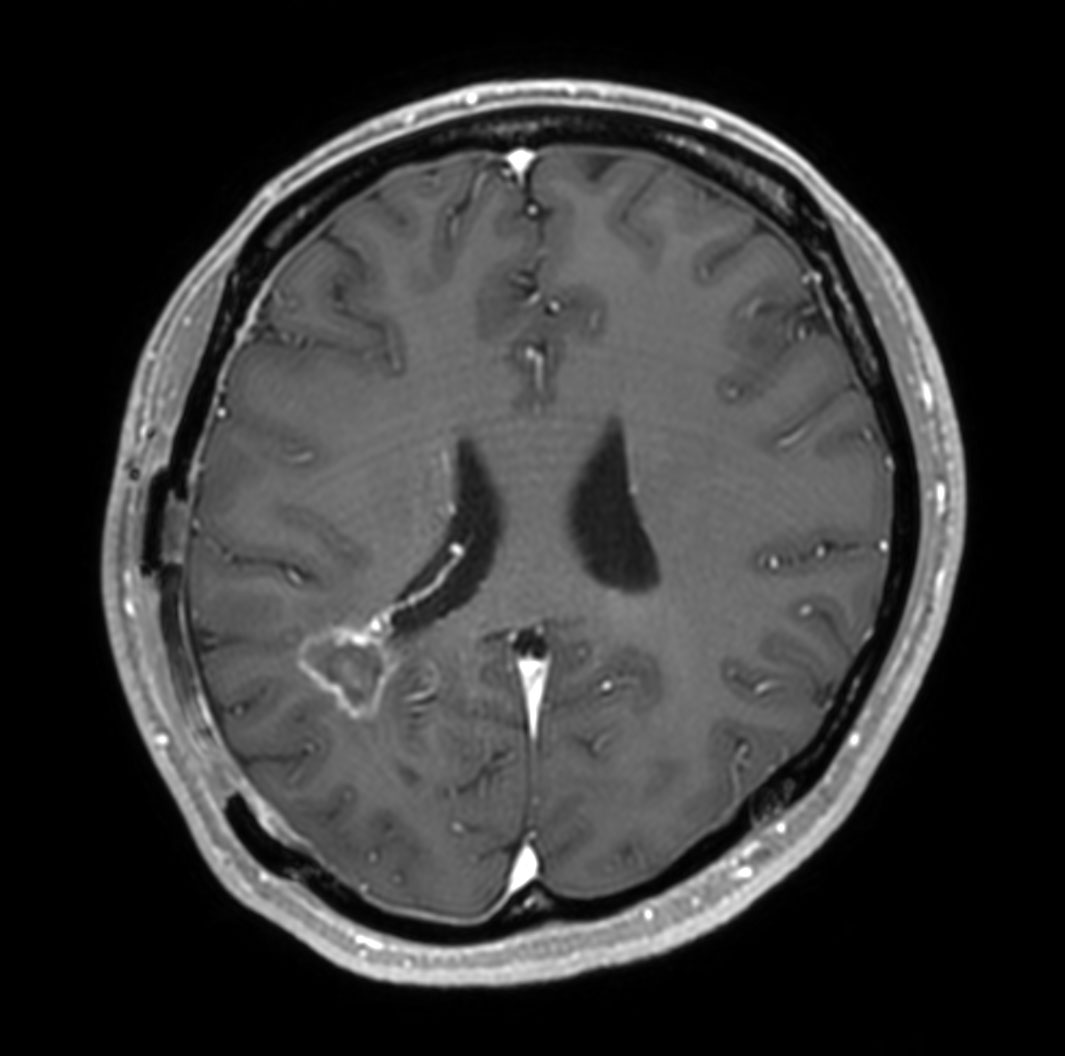

Patient with a glioblastoma recurrence. Glioblastoma was surgically removed 5 month ago. The gadolinium enhancement was first thought to be the enhancement of choroid plexus. However this was diagnosed recurrence of glioblastoma due to the high APT value.

Axial T1w IR TSE with gado